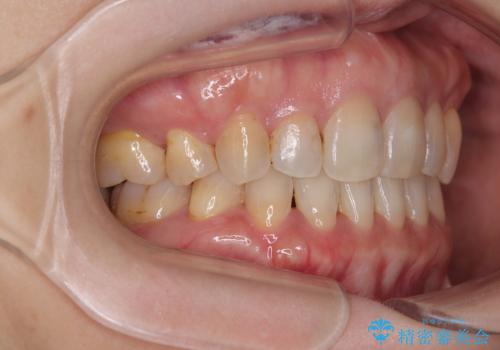

- 前歯のデコボコと口元の突出感を気にして来院された患者様です。

上下前歯がくちばしのように突出していたため、上下左右の第一小臼歯4本を抜歯し、ワイヤー装置にて矯正治療を行うこととしました。

上顎骨に対して下顎骨がやや前方位に位置しているため、歯肉退縮を回避するために下顎前歯をあまり内側に移動させることができない状況でしたが、十分に口元の突出感を改善することができました。